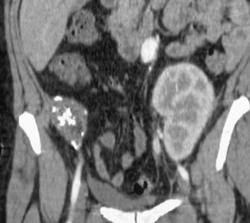

Accessory Renal Arteries to Lower Pole of Kidneys From Low Origins